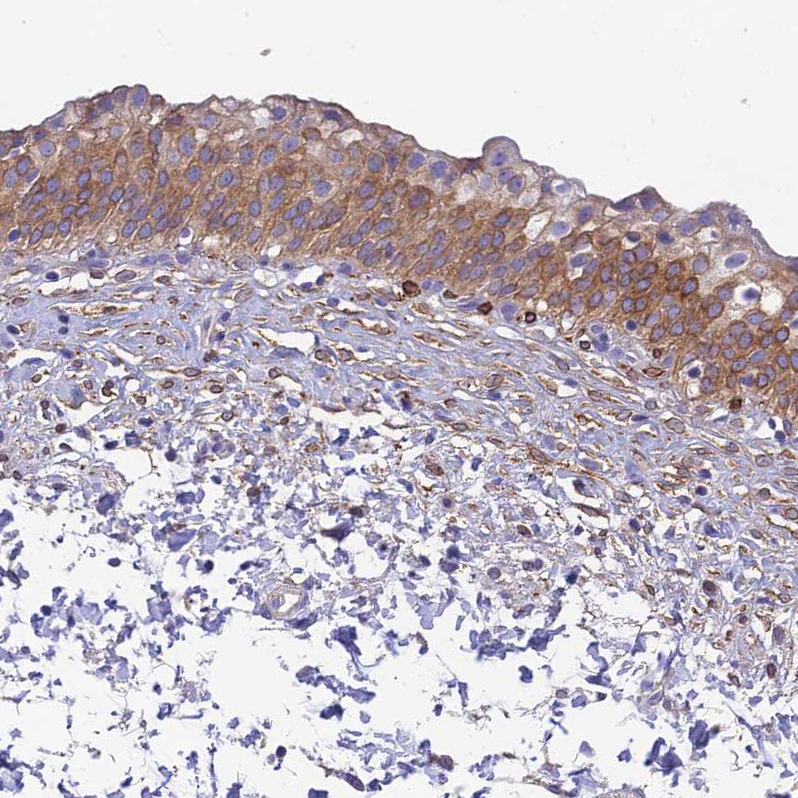

Immunohistochemistry analysis in human duodenum and testis tissues using HPA021826 antibody. Corresponding HSD17B2 RNA-seq data are presented for the same tissues.